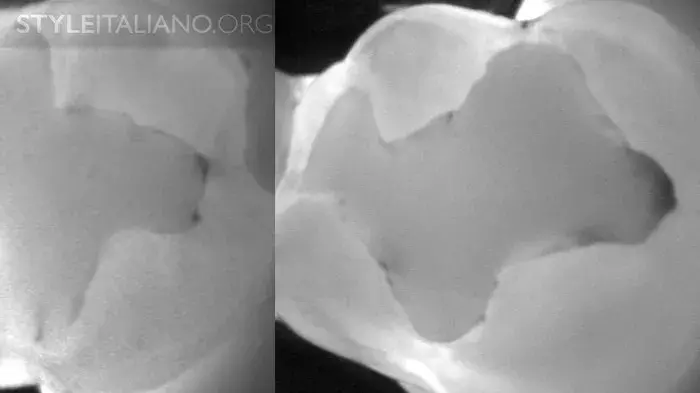

Рис. 3 Устройство Diagnocam, в основе которого лазерно-индуцированное просвечивание, позволяет нам просветить жевательные поверхности зубов. Выражается в серой шкале. Различные ткани зуба реагируют на свет по-разному: эмаль светлая, дентин более серый, а полости гораздо темнее.

DiFOTI (Digital Fiber Optic Trans Illumination) – здесь используется инфракрасное свечение.

Рис. 4 – Эта технология позволяет найти кариес на ранней стадии. Ткани серого цвета нуждаются в мониторинге.

Рис. 9 – Предварительная рентгенограмма. Скрытый кариес: кариес дентина на окклюзионной поверхности. Деминерализация достаточно большая, чтобы обнаружить ее с помощью просвечивания.

Рис. 16 – Просвечивание зубов показывает полости в истинном размере, а на рентгене они уменьшены.

Рис. 17 – Рентген слева, просвечивание справа.